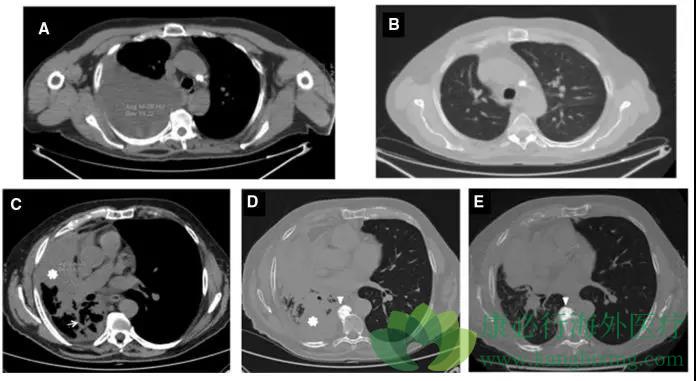

二、化疗后再挑战奥希替尼。临床多个研究发现,EGFR靶药耐药患者,使用化疗后有再次对靶药治疗敏感的现象,这里列举案例。68岁男性患者,肺腺癌骨转移,无症状脑转,L858R阳性。厄洛替尼耐药后出现T790M突变,患者使用奥希替尼,耐药后改用培美曲赛+顺铂化疗,培美曲赛维持治疗,期间血检T790M阴性,疾病控制。停止化疗8个月又出现进展,胸水检测T790M及L858R阳性,T790M由阴转阳,患者再用回奥希替尼,长期稳定控制。

图A为奥希替尼耐药后右肺严重胸水,图B为化疗后胸水控制住,图C和D为停止化疗后出现疾病进展,图E为再次使用奥希替尼后病灶明显缩小。案例中穿插的化疗很有可能根除了奥希替尼耐药相关癌细胞的增殖,让对EGFR靶药治疗敏感的癌细胞重新生长,逆转乾坤,使患者能再次从奥希替尼治疗获益。